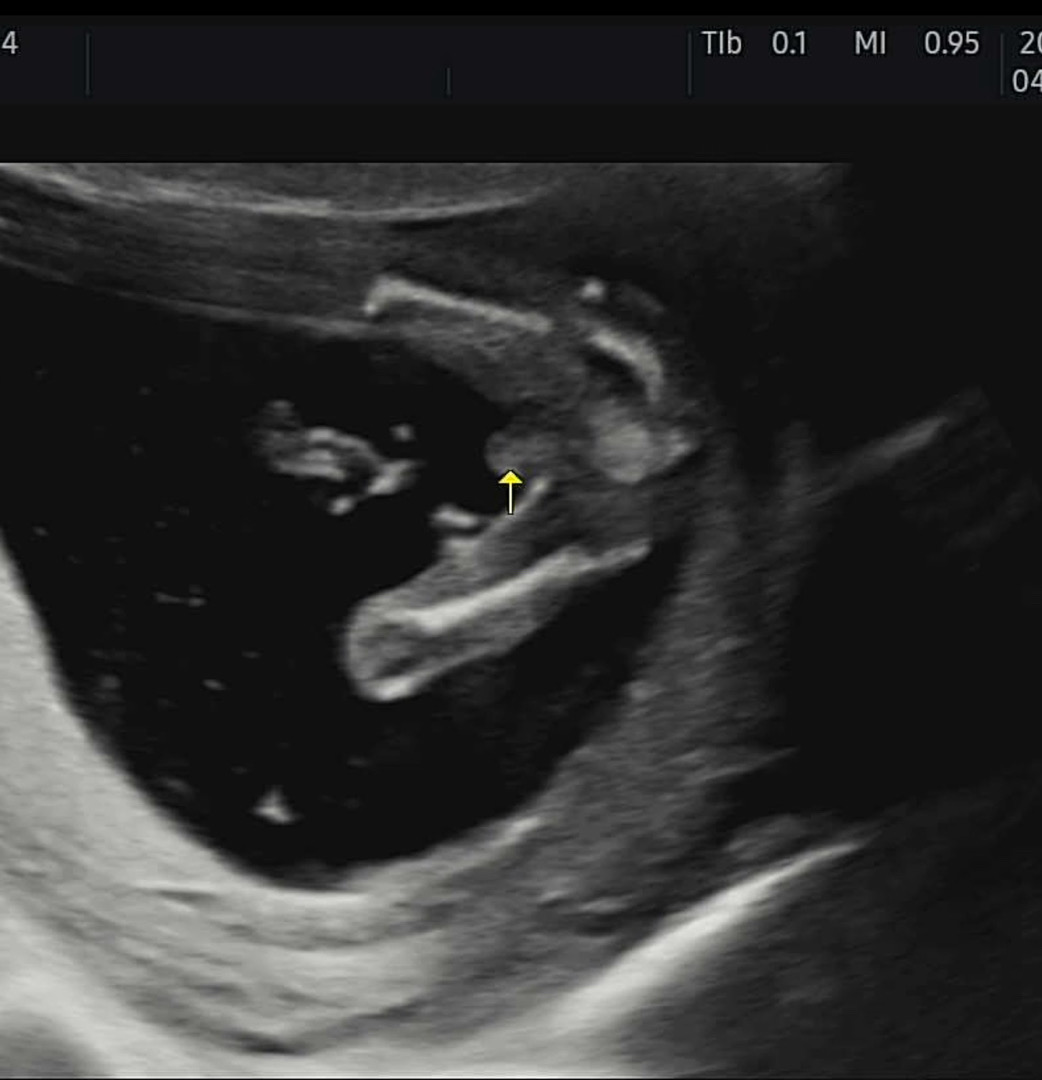

15주차이긴한데… 아무리 봐도 아들이겠죠? ㅠㅠ

아들같아요 !!

아들같아욤

헉 넘 볼록하네요 ㅎㅎ 귀여워요 아들같아요

15주차에 저정도면 아들인거같아효!